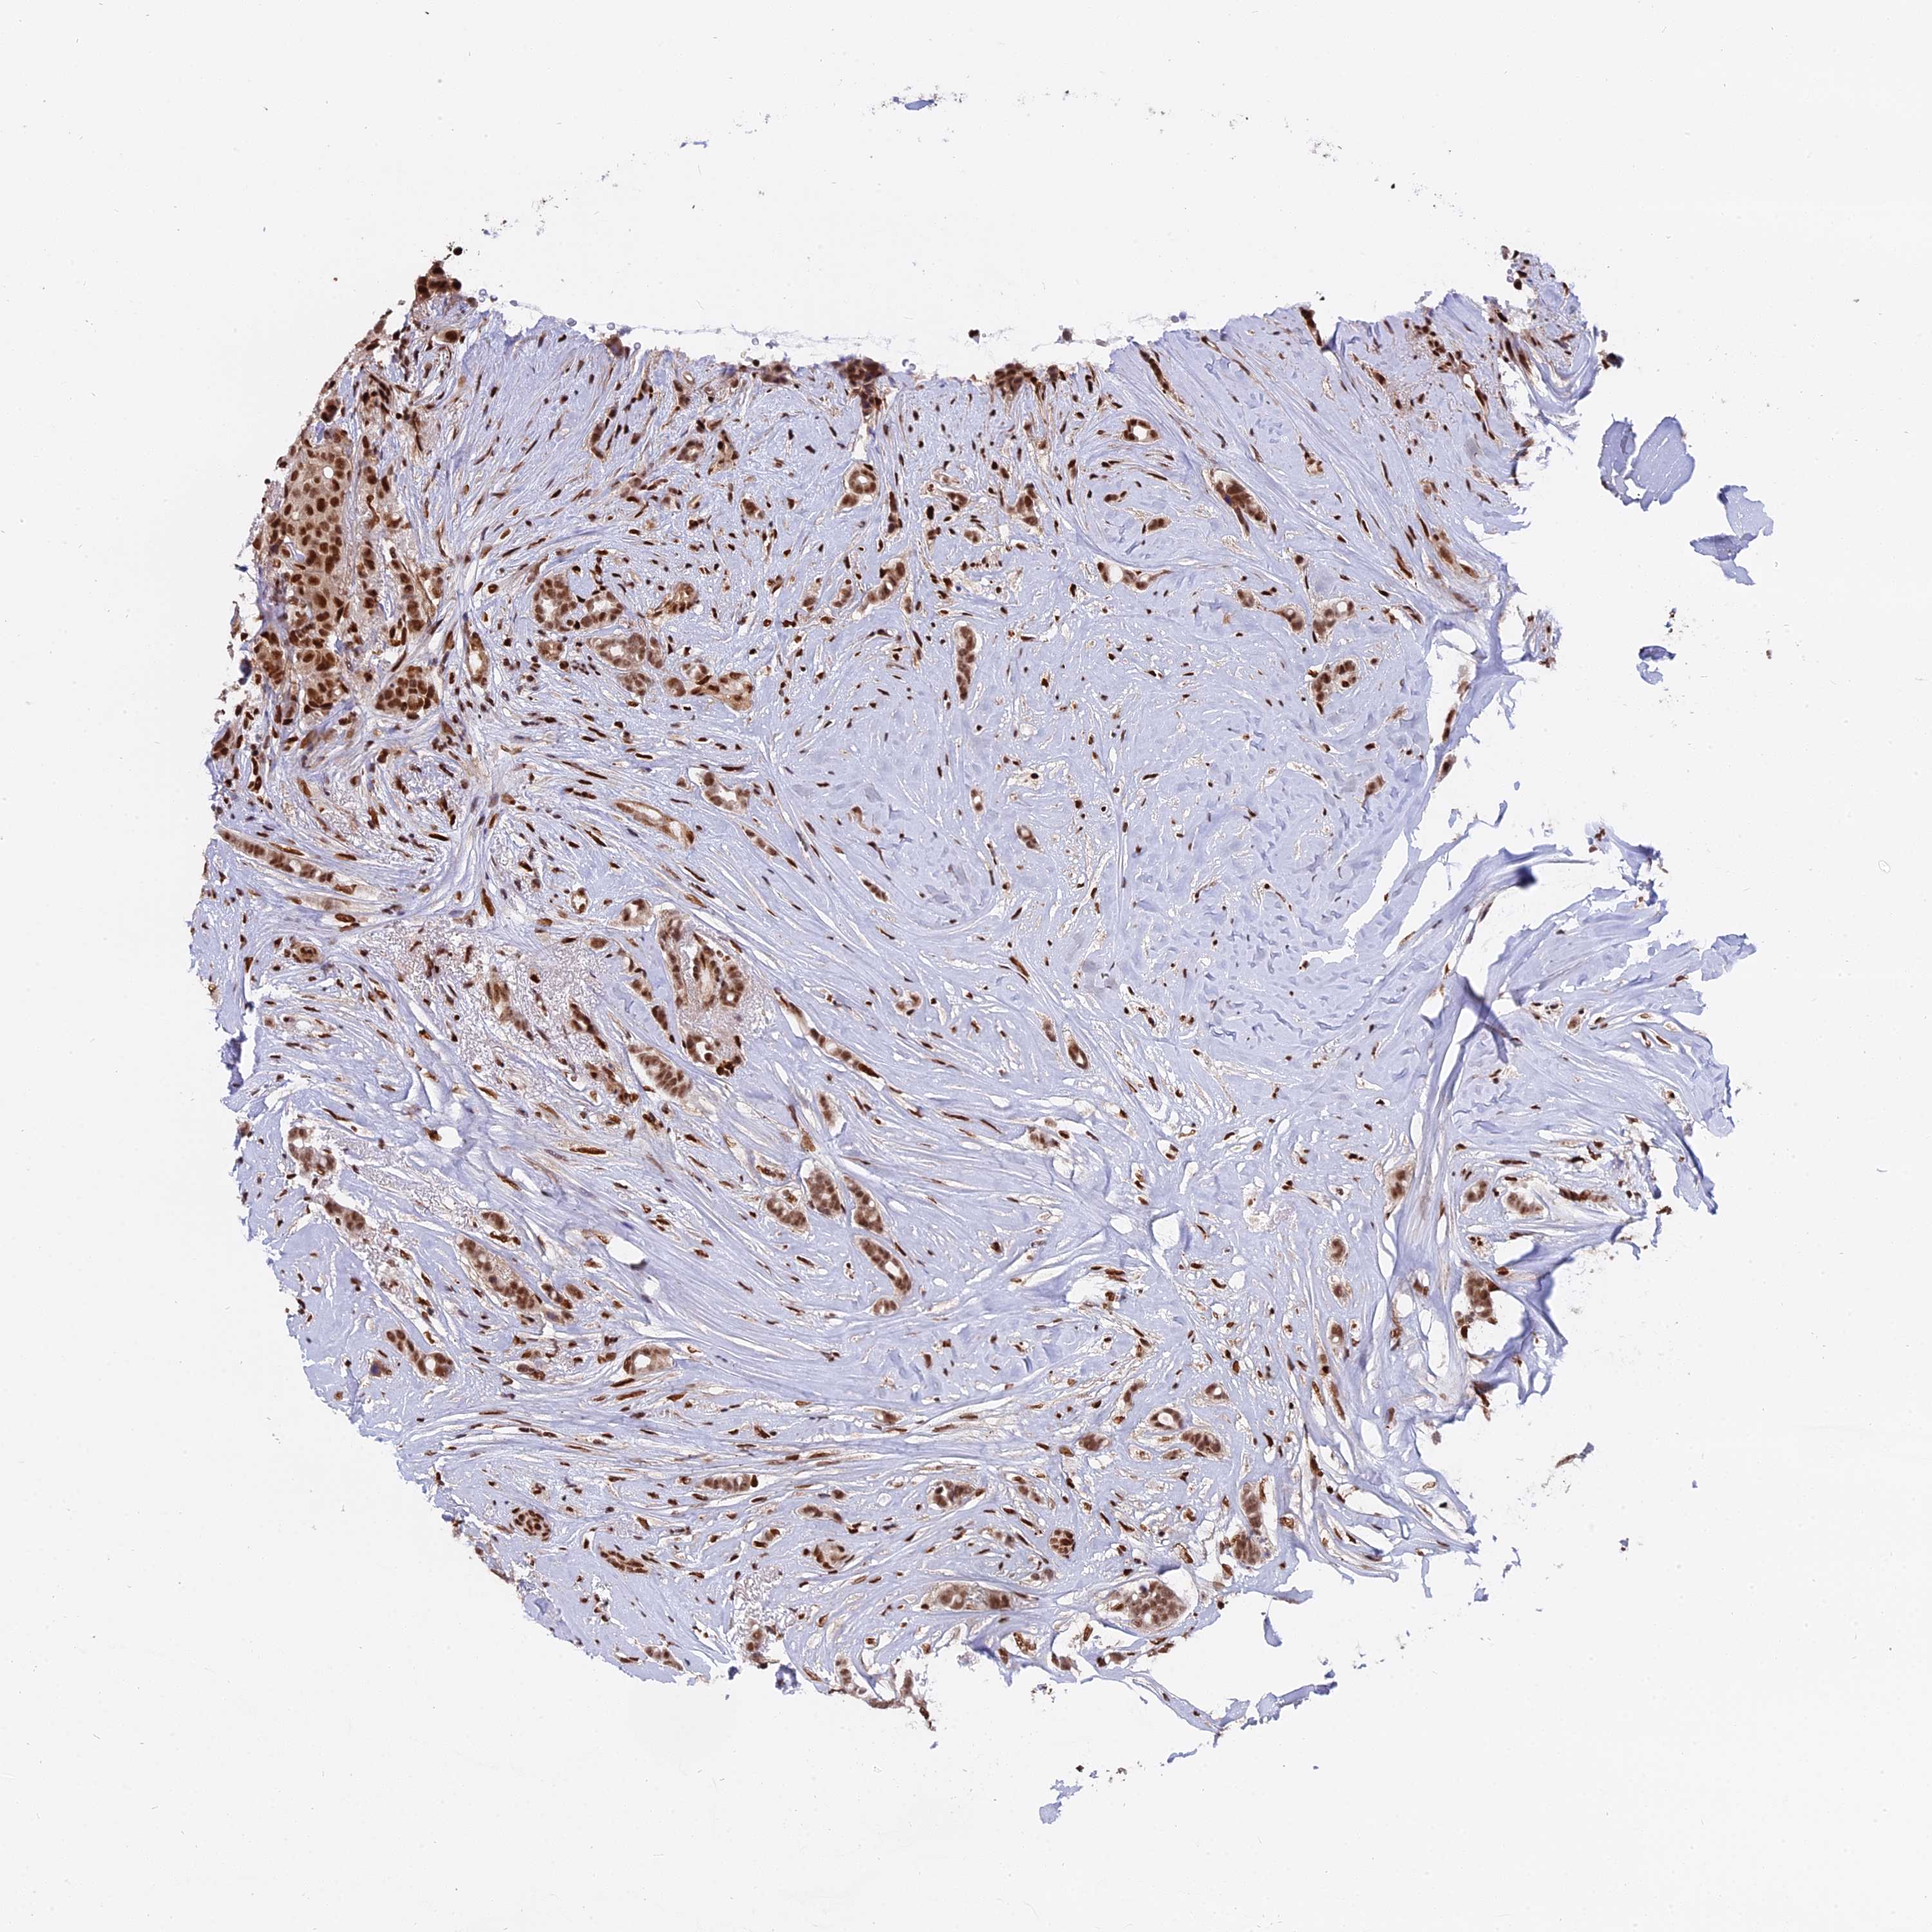

BRCA TCGA BRCA VALIDATION PROTEIN EXPRESSION